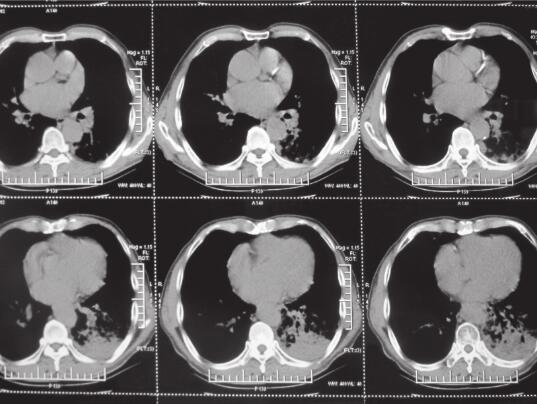

入院后给予抗感染(左氧氟沙星+头孢哌酮舒巴坦+伏立康唑)、祛痰等治疗,咳嗽、咳痰,间断发热等症状改善不明显。2014年3月7日肺部CT(图5)提示慢性支气管疾病肺气肿,伴双肺感染,左下肺不张。2014年3月11日支气管镜检查提示支气管腔内未见明显异常,左下叶黏性分泌物较多。保护性毛刷刷检培养无致病菌生长。2014年3月19日CT引导下经皮肺活检送病原学检查及病理检查提示黏液腺癌,组织培养无致病菌生长。

图5 2014年3月7日肺部CT提示左下肺大片状及右上叶片状阴影